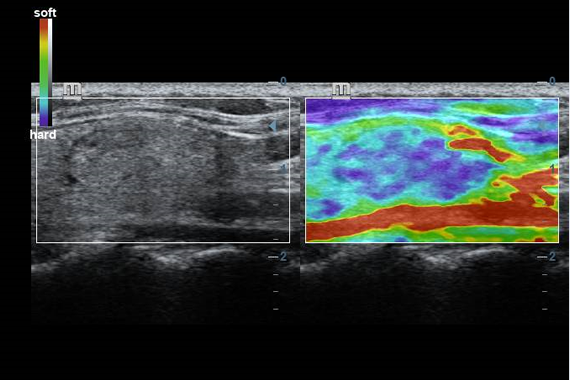

Клинические изображения

- Natural Touch Elastography - опция оценки эластичности ткани (эластография). Действует на линейных датчиках 7L4A, L12-3E и L14-6NE.